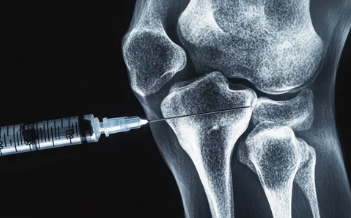

- 급성 발작 치료: 비스테로이드성 소염진통제(NSAIDs), 콜히친(Colchicine), 스테로이드 주사를 통해 염증과 통증을 완화합니다.